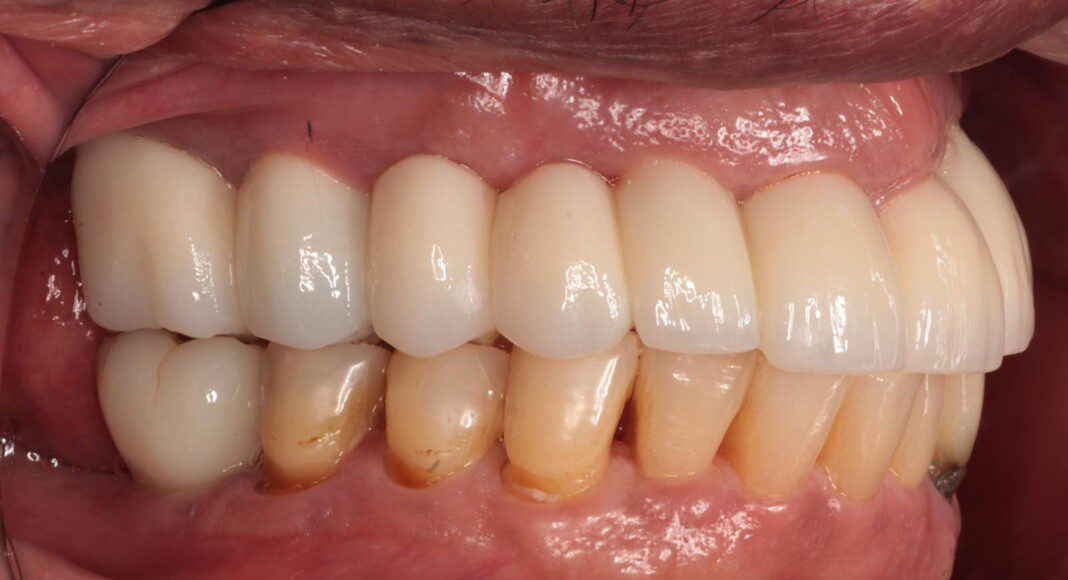

Left lateral (mirror) view of bridge. Existing implants (#s 10 and 12) are long. This is due to old implants being placed too deeply. As you will see in the smiling pictures, this does not adversely affect the outcome as the length of those teeth is not visible in his fullest smile.